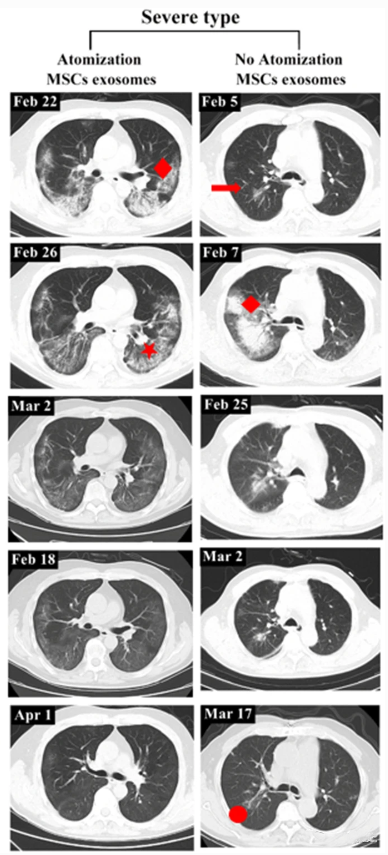

这一结果说明,早期干预不仅能加速病情恢复,还可避免肺部损伤的进一步恶化。对于轻症患者而言,快速康复的优势尤为明显。研究中还包括了一例重症患者,该患者自2020年2月27日开始接受外泌体雾化治疗,至3月18日的CT扫描结果显示,其双肺病变明显吸收,病变密度显著降低。到4月1日,患者肺部病灶完全吸收。相比之下,未接受外泌体雾化治疗的另一名重症患者,虽然肺部病灶也有所吸收,但依然残留纤维脐带样阴影,康复情况不及前者理想。

▲左:有外泌体雾化治疗的重症病例。右:无外泌体雾化治疗的重症病例